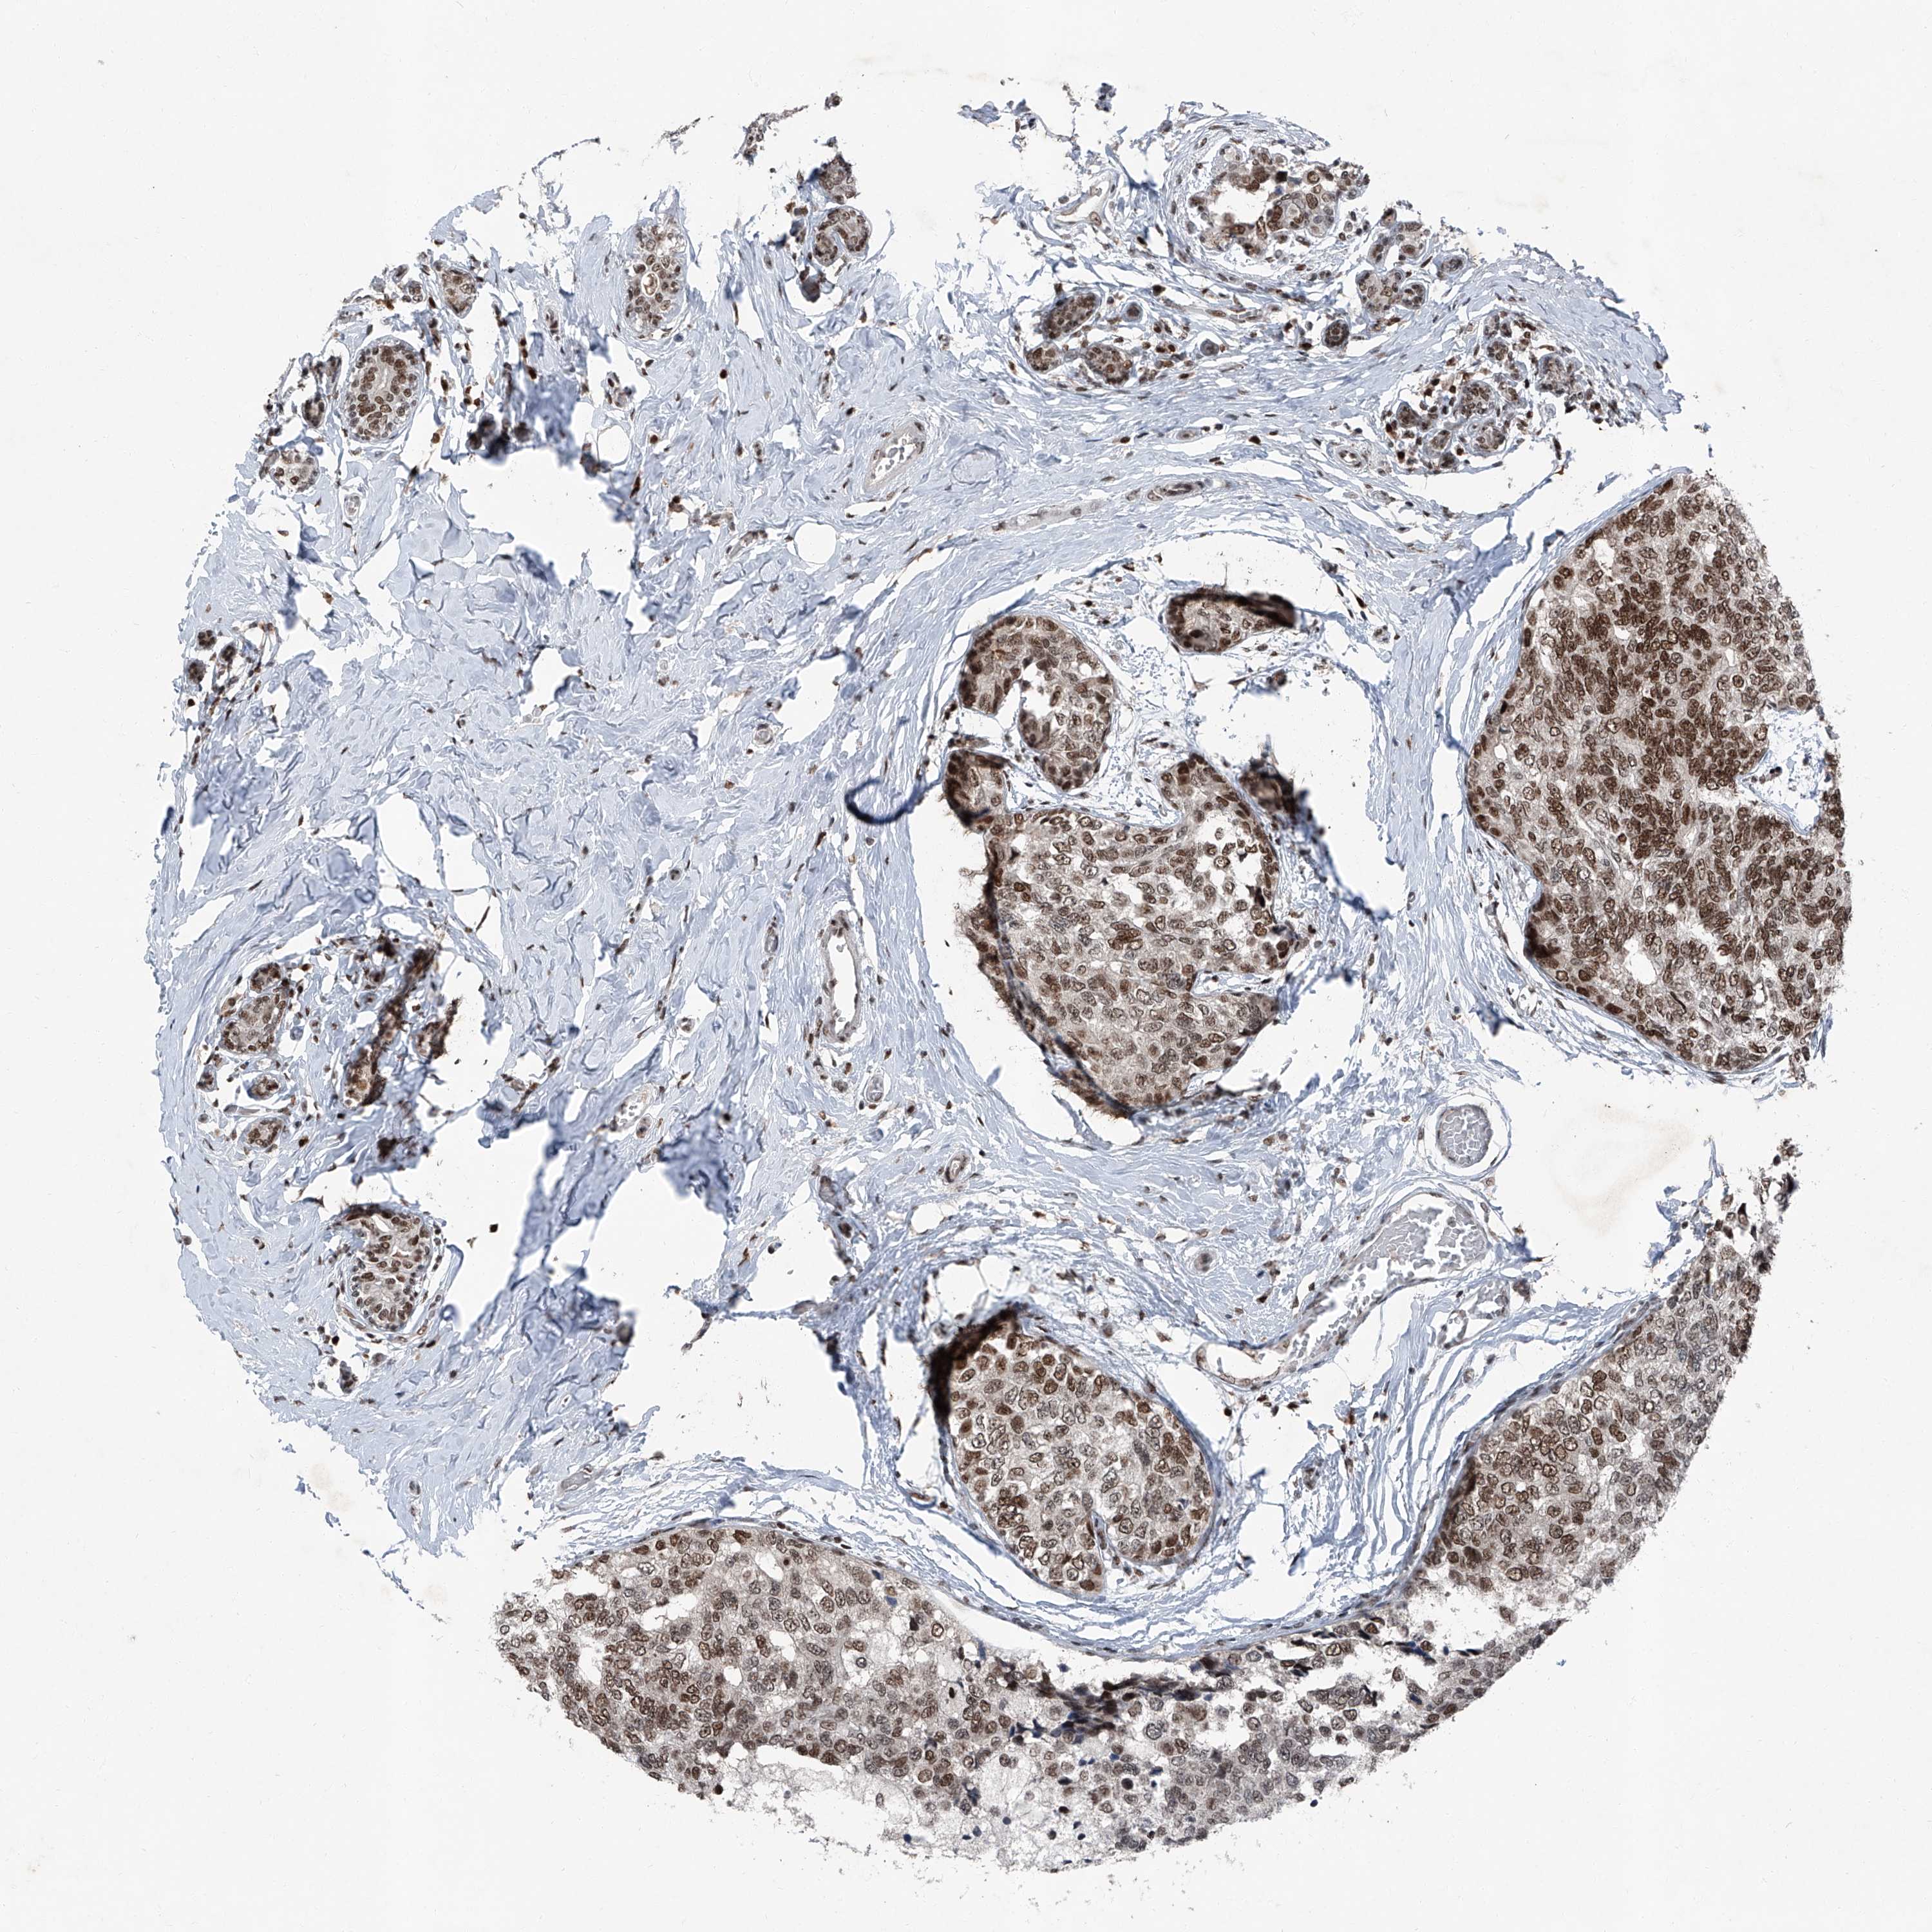

CANCER BREAST CANCER Show tissue menu

BRCA TCGA BRCA VALIDATION PROTEIN EXPRESSION